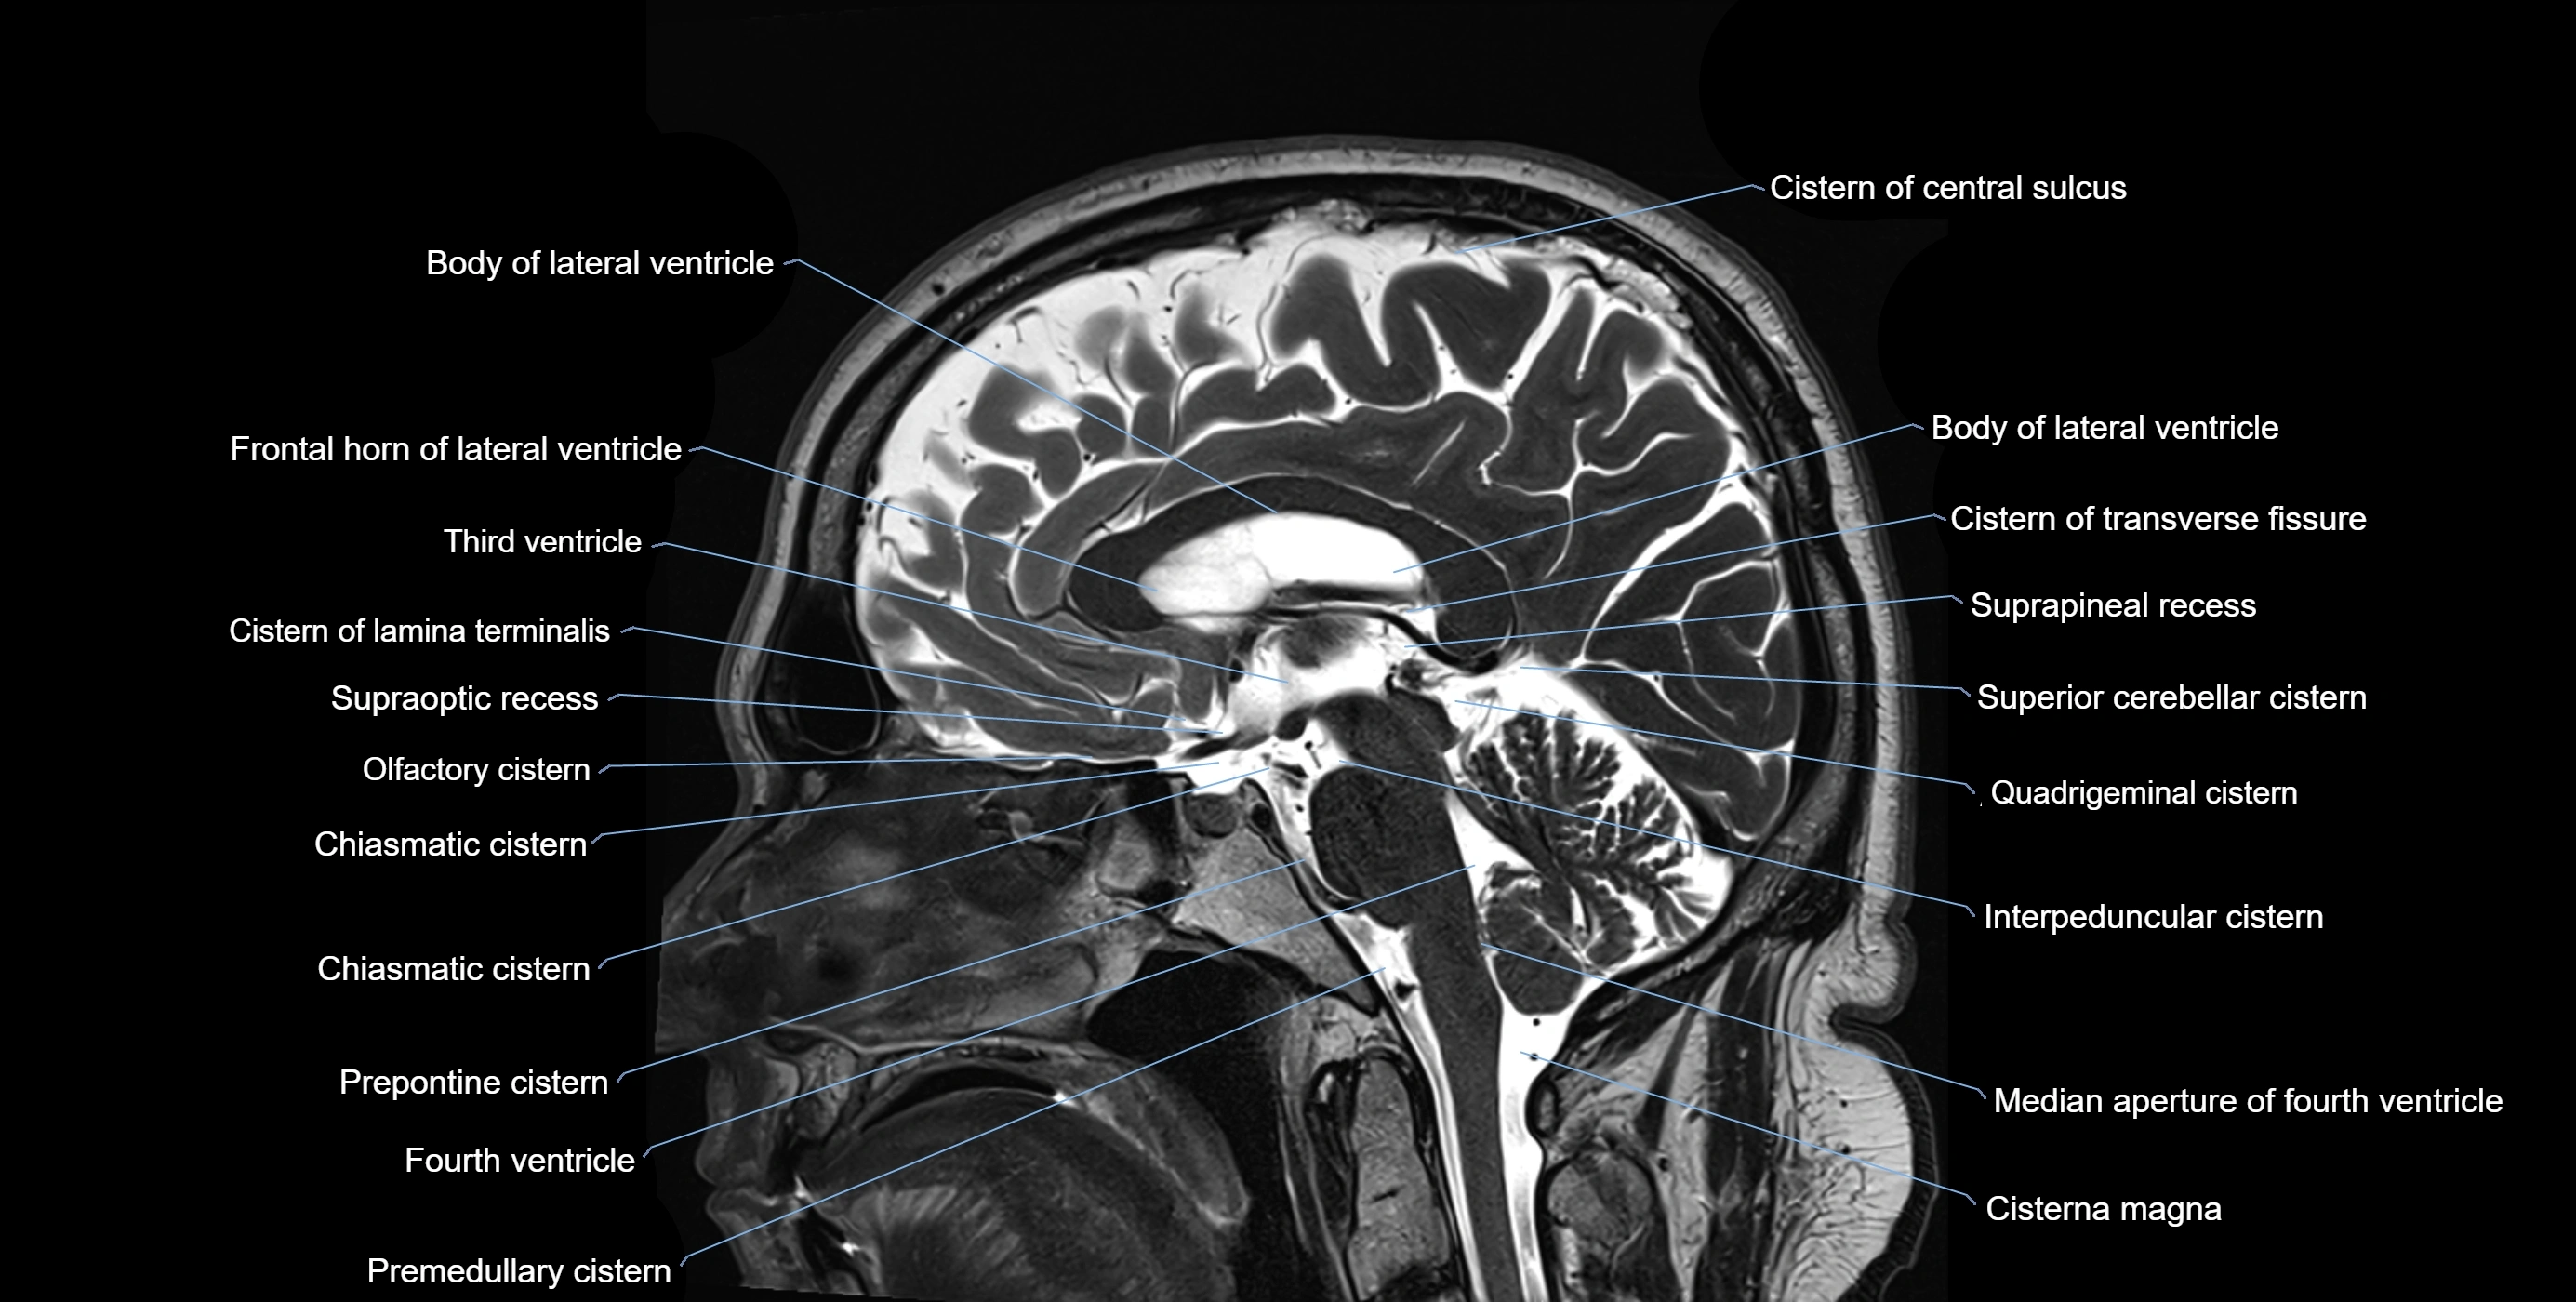

MRI images

image